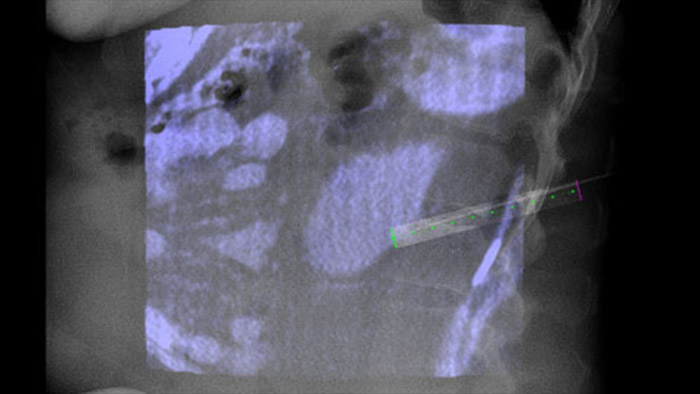

Dual View позволяет наложить 3D-изображение, полученное до процедуры (КТ/МРТ/ПЭТ-КТ), на двойное КТ-подобное 3D-изображение, полученное во время процедуры, для улучшения визуализации поражений и получения важных данных, необходимых для планирования траектории иглы.

Технология XperGuide обеспечивает точный визуальный контроль при ведении иглы к исследуемой области в режиме реального времени, накладывая изображения предварительно запланированной траектории на рентгеноскопические изображения3.